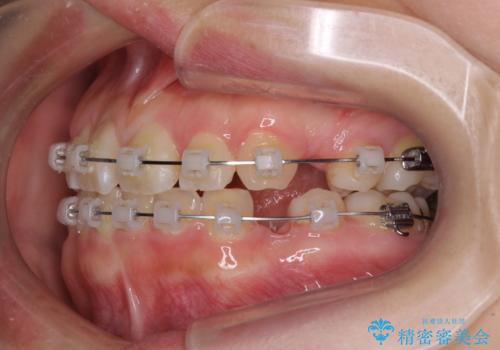

- クリアブラケット

親知らずの抜歯により埋もれた奥歯周辺の歯肉が切除され、矯正装置が装着できるようになりました。

奥歯の移動、特に下顎大臼歯の移動は時間がかかることが多く、3年以上の治療期間を想定していましたが、想像以上に動きがよく、2年強で終えることができました。